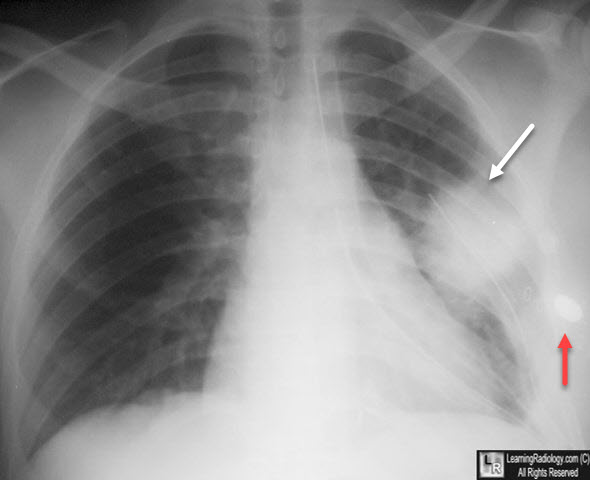

View Lung Contusion Chest X Ray UK. Many clinical conditions can be evaluated by this simple radiology test. Trauma (contusion), immunologic (goodpasture's), bleeding diathesis, pulmonary embolism.

Associated with signs of volume loss. The consolidation seen in the. Outcomes for lung cancer are relatively poor compared with the healthcare systems of many other advanced economies, which make more extensive use of other imaging modalities such as computed tomography (ct). To check on any catheters and chest tubes you may have.